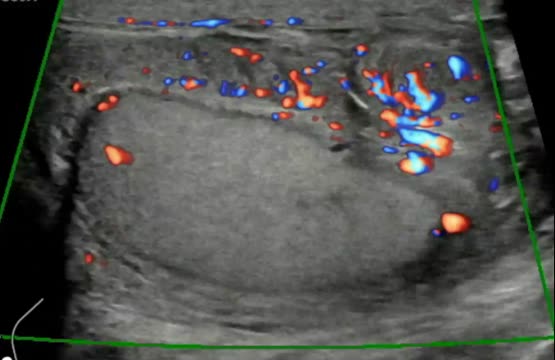

En varones mayores de 60 años, el tumor testicular maligno más frecuente es el linfoma, tratándose normalmente de un linfoma no Hodgkin que presenta un peor pronóstico. Suele ser en su mayoría unilateral y la ecografía nos muestra un testículo de mayor tamaño con un parénquima difusamente hipoecogénico (fig. 2c) con aumento del flujo sanguíneo, o lesiones hipoecogénicas multifocales.

Cortes longitudinales de masas testiculares: a) Masa intratesticular homogénea e hipoecogénica (medida en ejes longitudinal y anteroposterior con línea discontinua amarilla) con diagnóstico anatomopatológico de seminoma; b) Imagen a con captación Doppler color; c) Masa que ocupa la práctica totalidad del teste (medido en ejes longitudinal y anteroposterior con línea discontinua amarilla) hipoecogénica con diagnóstico anatomopatológico de linfoma.